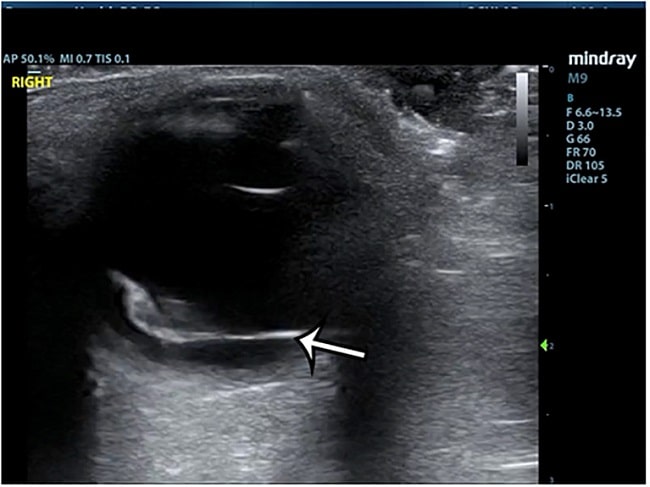

Kendala-kendala ini menyebabkan point-of-care ultrasonography (POCUS) okular mulai digunakan sebagai alternatif untuk memeriksa segmen posterior mata, termasuk mendiagnosis ablatio retina. POCUS menggunakan mesin ultrasound portable yang bisa dilakukan di bedside dengan cepat, aman, dan noninvasif oleh dokter UGD yang sudah terlatih. Hal ini bermanfaat karena dokter spesialis mata tidak selalu ada di UGD, terutama di luar jam kerja.[1–4,7,8]

Studi mengenai akurasi POCUS untuk mendiagnosis ablatio retina pada setting UGD telah banyak dilakukan. Sensitivitas dan spesifisitas yang dilaporkan beragam, tetapi mayoritas studi menunjukkan hasil yang menjanjikan.